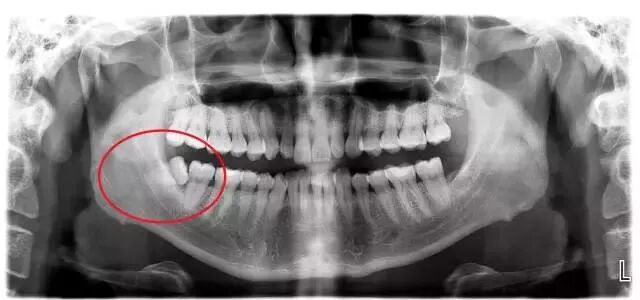

看看上图这些智齿的生长位置,真是千奇百怪。你觉得那颗最好拔?智齿但一旦生长位置出现了偏差,那就得科普另外一个词,阻生智齿

▲阻生智齿

智齿在颌骨内由于位置不当,不能萌出到正常咬合位置,被称为阻生智齿。阻生智齿必须拔除,并且拔除的难度远远大于一般智齿。

这种情况你只有通过拍摄口腔全景片才能看清:看牙为啥要拍片?看牙不拍片如同开车无驾照!